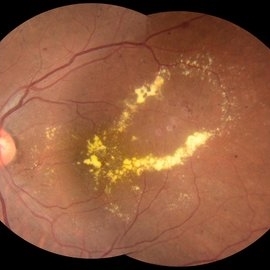

Leaking Aneurysms in Diabetic Retinopathy

Mar 22 2024 by Vaidehi Sathaye

Fundus photograph of LE of a 50 year old female with leaking aneurysms encircled by hard exudates, as a sequelae of Diabetic Retinopathy.

Photographer: Dr. Vaidehi Sathaye

Imaging device: Topcon

Condition/keywords: aneurysm, diabetic retinopathy, hard exudates